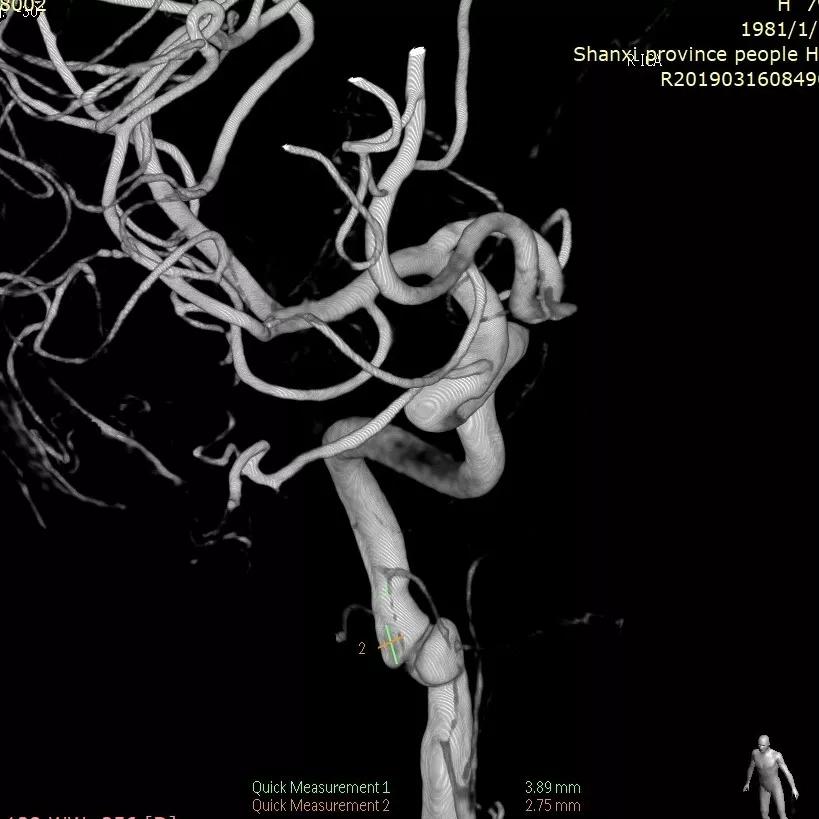

男,62y,因“突发头痛伴恶心呕吐1天”来院。

患者于入院前1天无明显诱因突发头。外院头颅CTA示:颅内动脉瘤。我院行DSA示:左侧大脑中动脉动脉瘤。

全脑血管造影可见左侧大脑中动脉动脉瘤,瘤体最大径:16.7mm,瘤颈宽:8.3mm。

Synchro 14微导丝导引支架导管,远端送入左侧中动脉下干远端困难,支架导管内穿行Tracxseed微导丝,双导丝导引支架导管顺利进入左侧中动脉下干远端,尾部链接Y阀1个,压力带1个。

经支架导管,置入Tubridge® 3.0×30mm,释放位置良好。

复查造影,动脉瘤造影剂明显滞留,各血管及分支通畅,流速正常。手术结束。